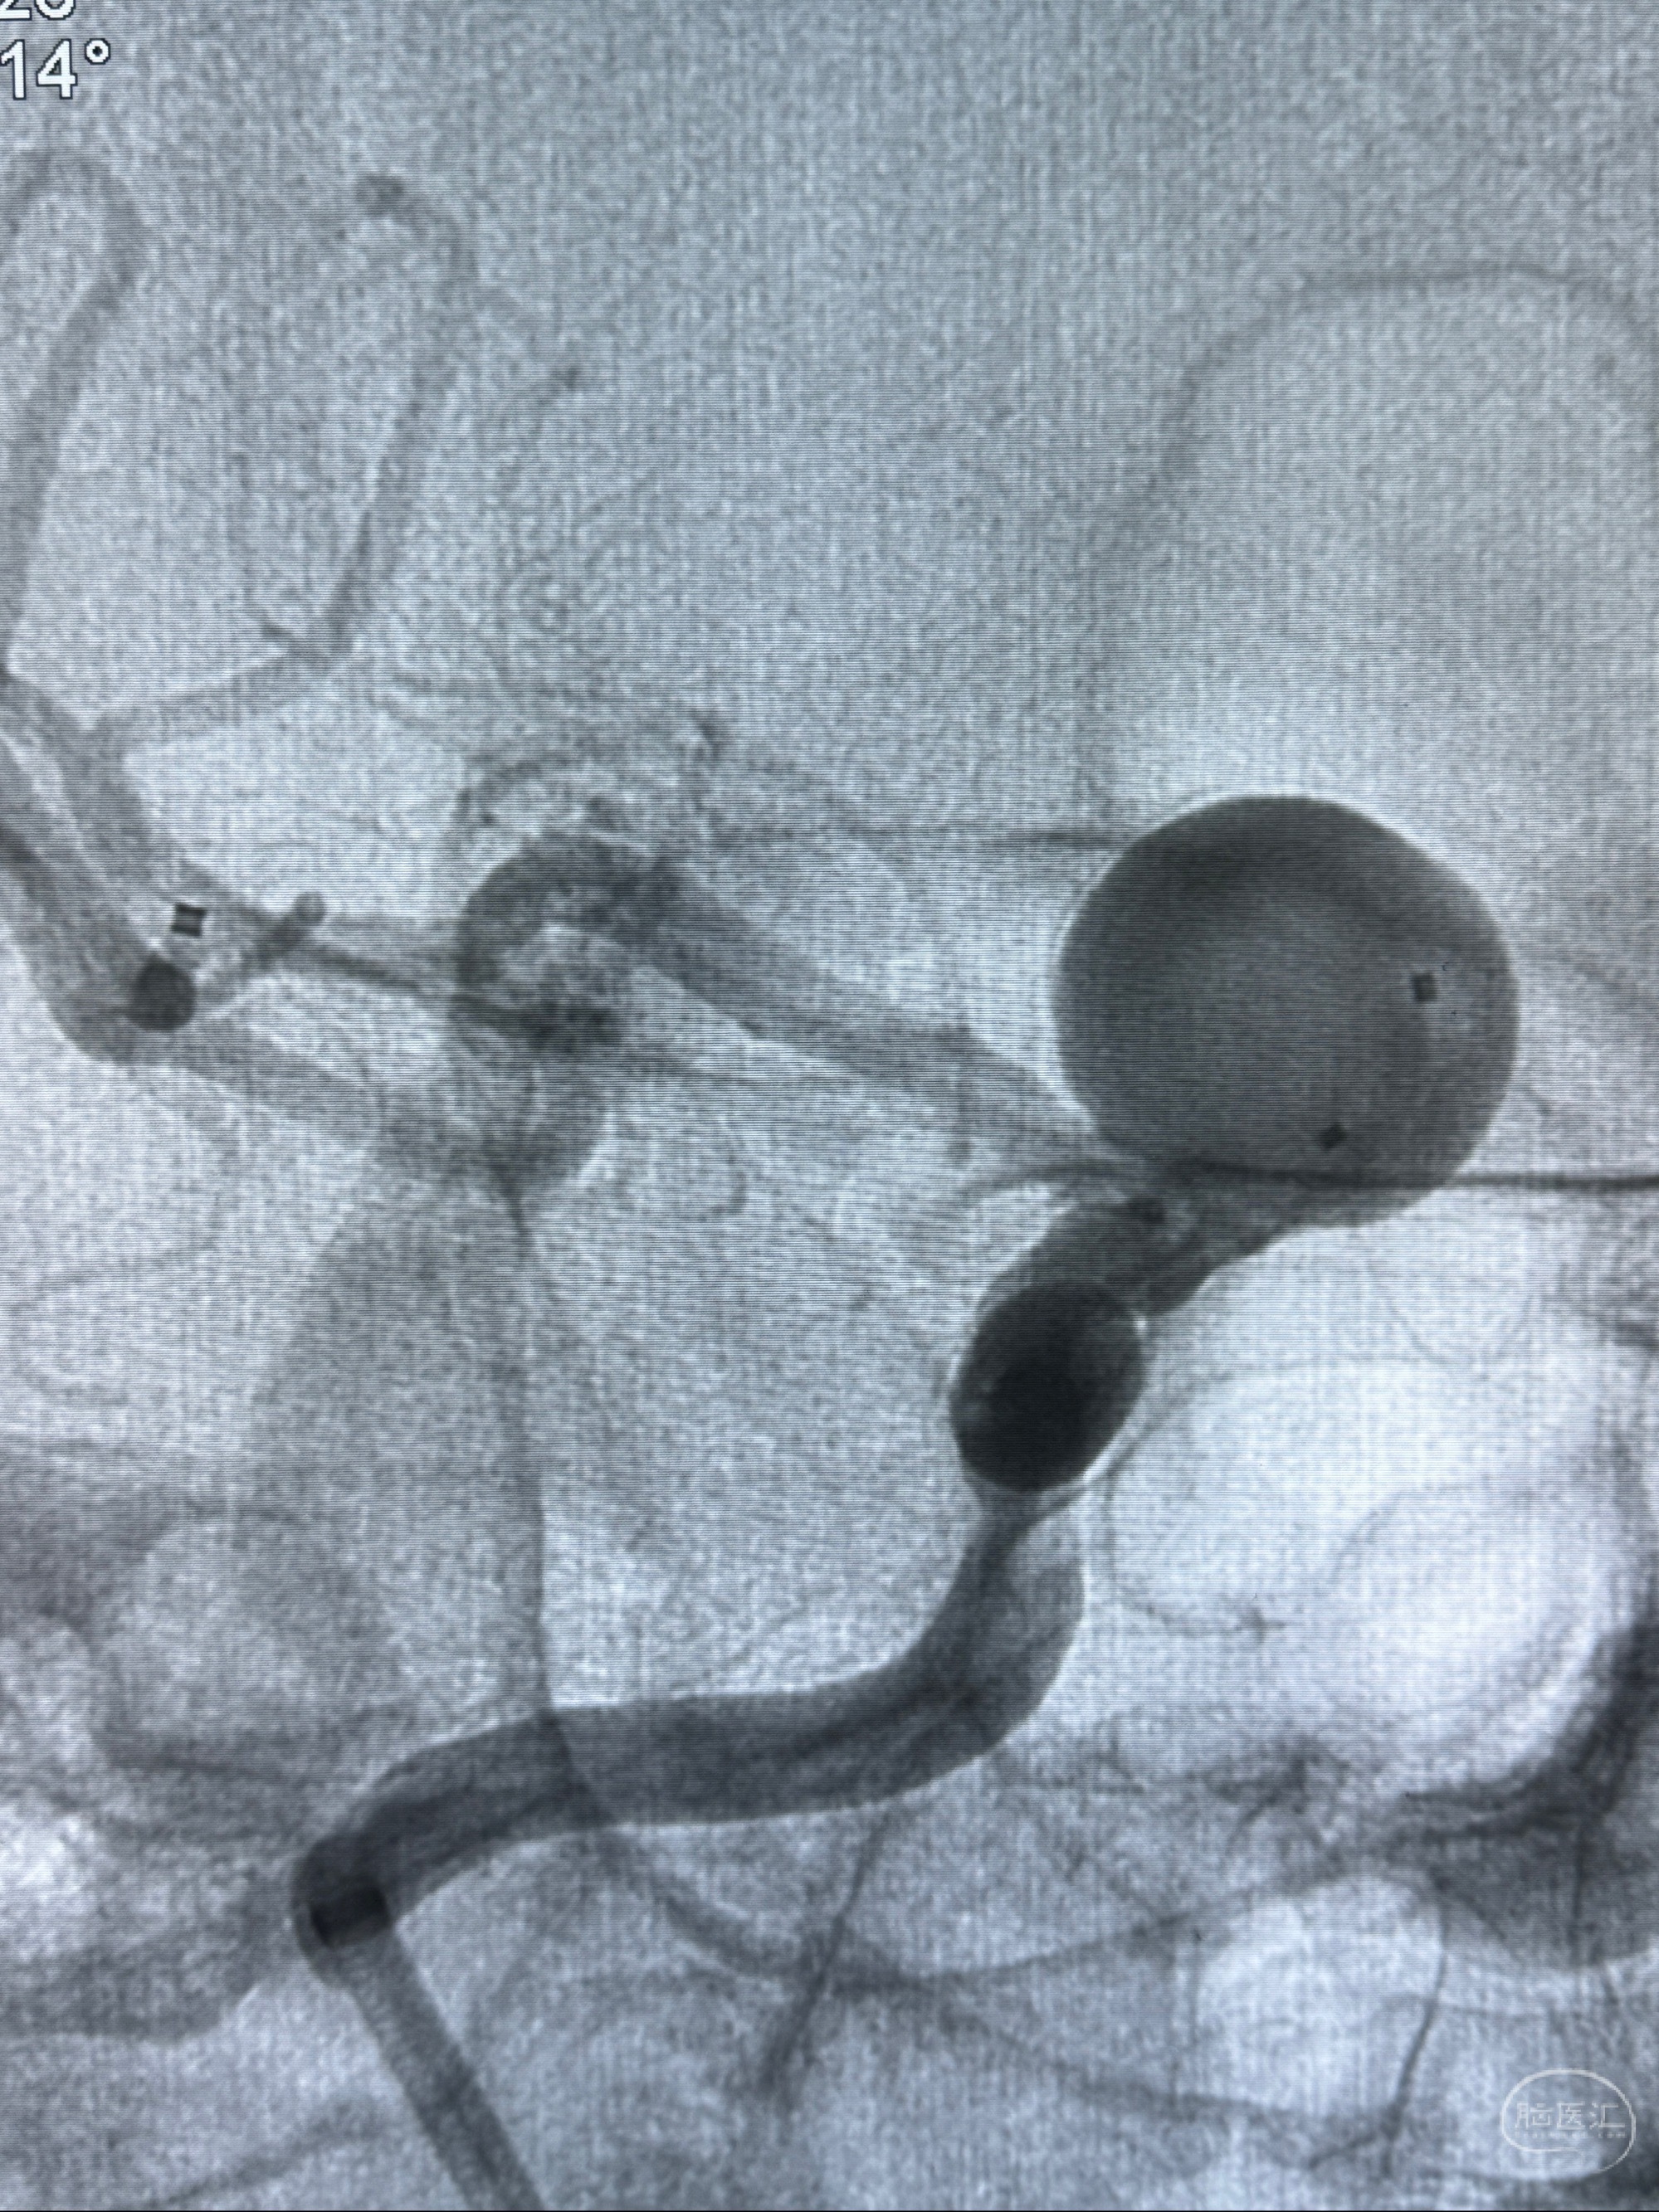

现病史:患者诉2年来反复发作性头痛,顶枕部为主,因自己考虑高血压可能,未予系统检查;患者约20日前无明显诱因下突发剧烈头晕,有天旋地转感,不能睁眼,伴视物模糊;外院查头颅MRI+MRA提示:左侧颈内动脉C6段动脉瘤;遂至复旦大学附属华山医院就诊,于2023-12-08行全脑血管造影提示:右侧颈内动脉C6段动脉瘤,瘤颈6.68mm,动脉瘤大小13.28*12.34mm,建议行密网支架辅助栓塞术治疗,因缺乏相关材料遂出院。现患者仍有顶枕部头痛不适,为求进一步诊疗脑血管病变至我科就诊,收治入院。

2023-12-08 复旦大学附属华山医院 全脑血管造影:右侧颈内动脉C6段动脉瘤,瘤颈6.68mm,动脉瘤大小13.28*12.34mm

2023-12-08外院DSA:右侧颈眼动脉瘤,约13*12mm大小,压颈试验显示左右向及后向前代偿可

测量动脉瘤的大小:16*13.8*7.6mm大小,较原先变大,考虑双抗后瘤内血栓溶解可能